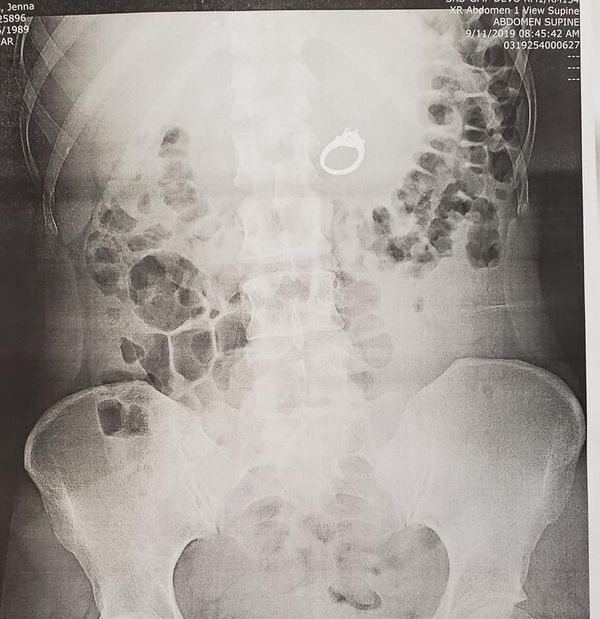

X-Ray taraması ile midesinde görüntülenen 2.4 karatlık nişan yüzüğün doğal yollarla vücuttan atılmasının iyi bir fikir olmadığı konusunda anlaşan doktorlar, Evans'ın ameliyat olması gerektiğini söylediler.